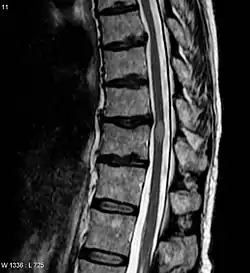

![]() صورة بالرنين المغناطيسي توضح آفة بسبب التهاب النخاع المستعرض (الآفة هي اللون الأفتح، شكلها بيضوي في المركز باتجاه اليمين)، أخذت هذه الصورة بعد 3 أشهر من تعافي المريض. صورة بالرنين المغناطيسي توضح آفة بسبب التهاب النخاع المستعرض (الآفة هي اللون الأفتح، شكلها بيضوي في المركز باتجاه اليمين)، أخذت هذه الصورة بعد 3 أشهر من تعافي المريض. | |